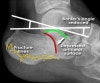

Bohler’s angle < 20° indicates fracture

X-ray : Normal calcaneus(Lateral view)

X-ray : 종골 골절(Calcaneal fracture) - Lateral view

1. Flattening of Bohler's angle

2. Depression of the articular surface of the posterior subtalar joint (red line)

from its normal position (green line)

3. Fracture lines can be seen passing through the calcaneus